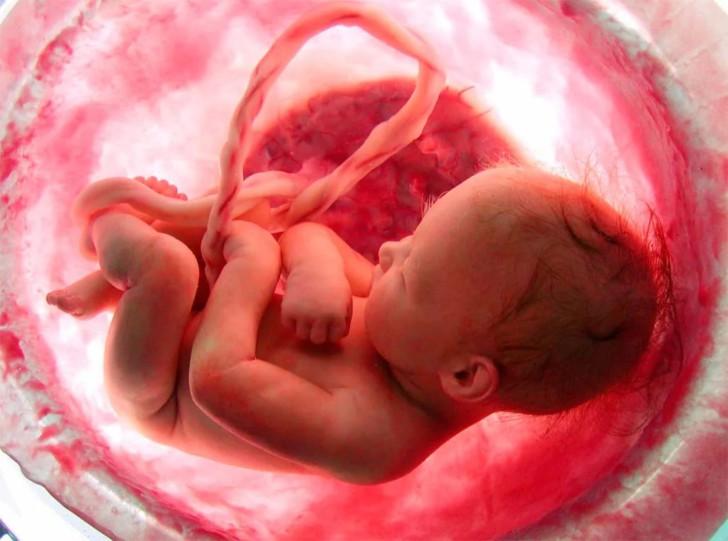

Что такое плацента, какую функцию она выполняет у беременных женщин, что происходит после родов?

Плацента при беременности формируется с момента оплодотворения женщины. Она растет и меняется одновременно с ребенком по мере изменения его потребностей. Плацента при беременности выполняет...